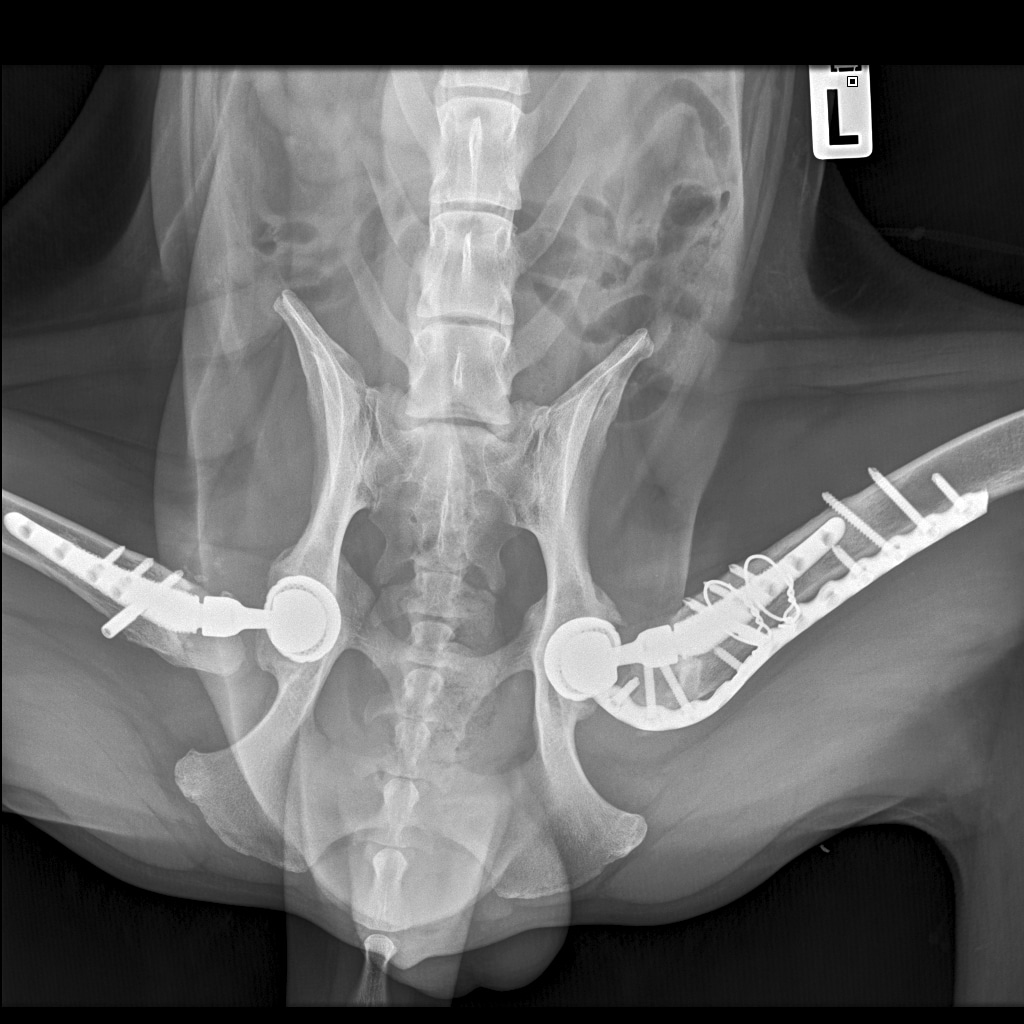

Выписка